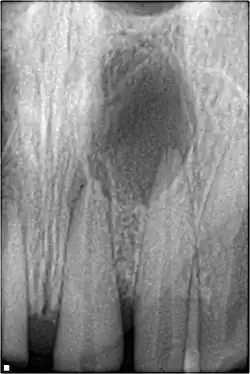

| A broken upper front tooth. The layers of tissue that make up the tooth are clearly visible, with the pink pulp standing out against the paler dentine and tooth enamel. | |